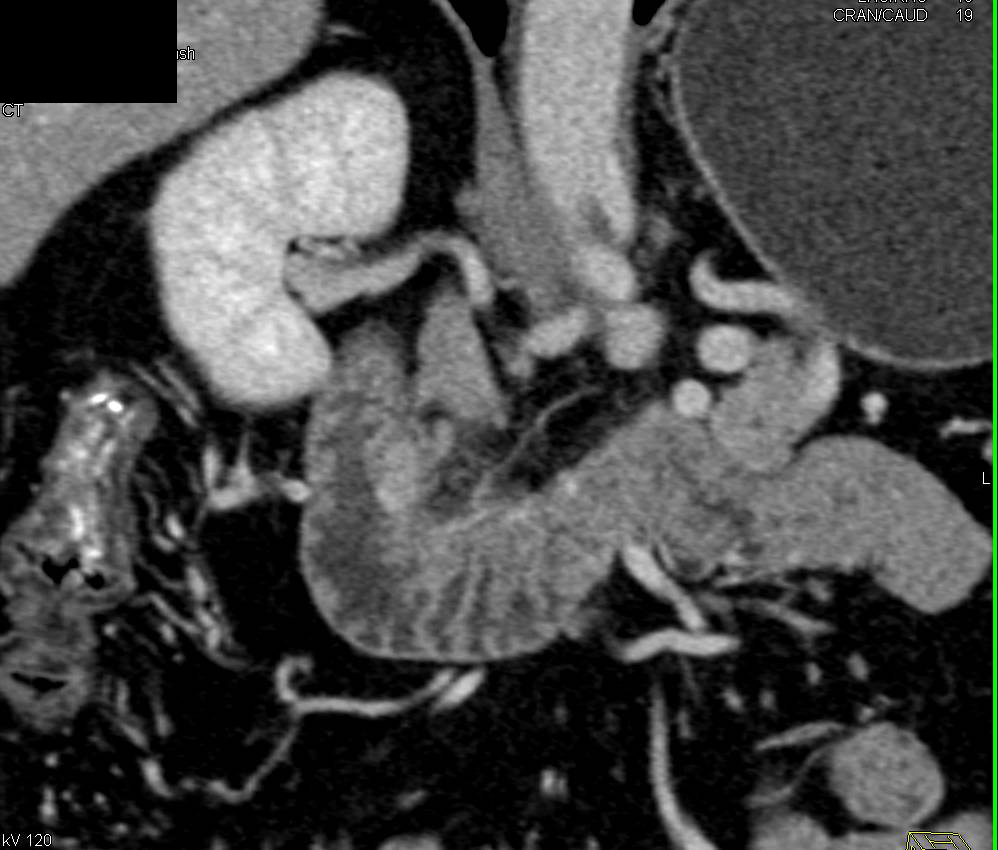

Renal Cell Carcinoma Recurrence with Multiple Enhancing Pancreatic Metastases